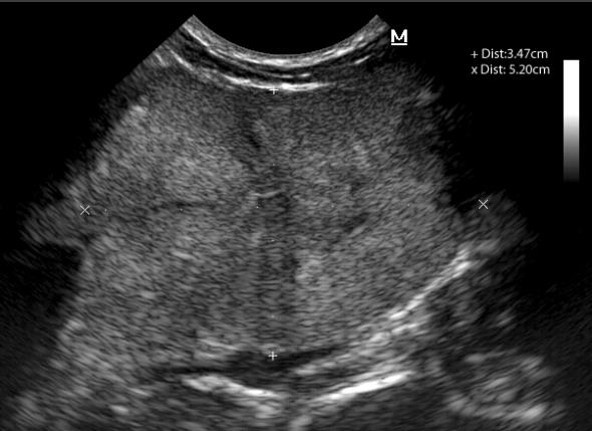

How does the overall echogenicity compare to the normal prostate?

What is the liekly diagnosis?

Hypoechoic

More heterogenous (marbled appearance)

Slightly enlarged

Likely Diagnosis:

Acute prostatitis ** was this

Neoplasia possible

Note: there are not enough fluid cavities for cystic disease